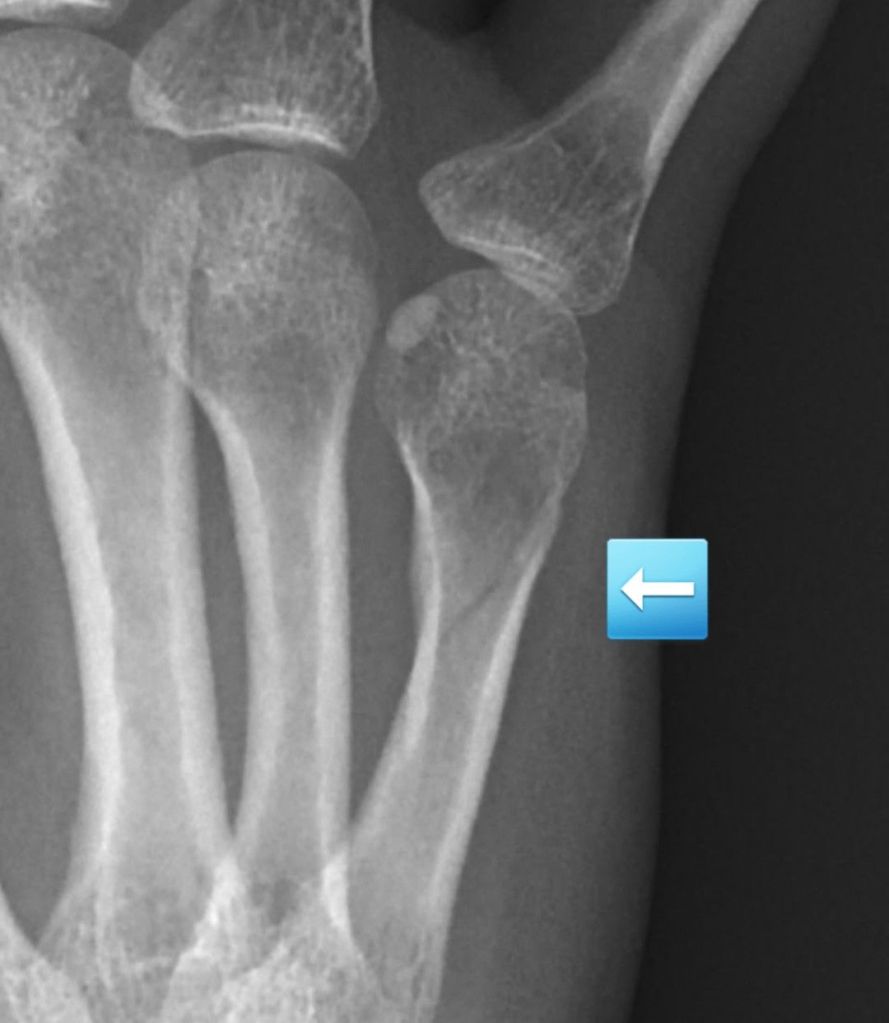

The x-ray confirmed a nondisplaced fracture of my fifth metacarpal, the bone in your hand that attaches to the pinky finger. I was bummed about not getting to use my new exerciser, but happy that the fracture was small and should have no issues healing.

A perk of my job is having a great work family. I walked to the orthopedic department next door and told one of the providers what was happening. They looked at the x-ray and agreed with the radiologist that it was a simple fracture. I was given a splint to wear. The fracture was so insignificant it did not even need to be put in a cast.

It was important to keep my fingers straight. However, the spasms were constantly hyperextending them. Then a new phenomenon started. After my fingers splayed out in unnatural positions after a spasm, they would snap closed into a clenched fist. I could not stop it. I had zero control over my own hand. The pain when my fingers closed would steal the air from my lungs as I gasped in both pain and surprise. I did not need an x-ray to know the fracture was worsening. The pain, my disfigured hand, and the continued bruising and swelling were enough.

Nevertheless, three weeks rolled around and it was time to take another x-ray. I looked at my coworker as he placed the lead apron over my lap and chest and told him I did not expect good news. He said it would be fine. We say that to all our patients. I knew better though. After the second image, he returned to the room shaking his head. “You’re right”, he said.

My nondisplaced fracture had completely shifted. If it had been a larger bone, it would have protruded from the skin. I went from an uncomplicated break that did not even need a cast to now needing surgery. My world crumbled. I was immediately terrified and overwhelmed with thoughts. My anxiety took control. I was afraid of the consequences of the anesthesia on my MS. I was terrified of not being able to use my hand for an extended period and whether I would ever regain strength and function. I was worried about the sick time I would have to blow through. I need that time for when I truly am disabled and can no longer work.